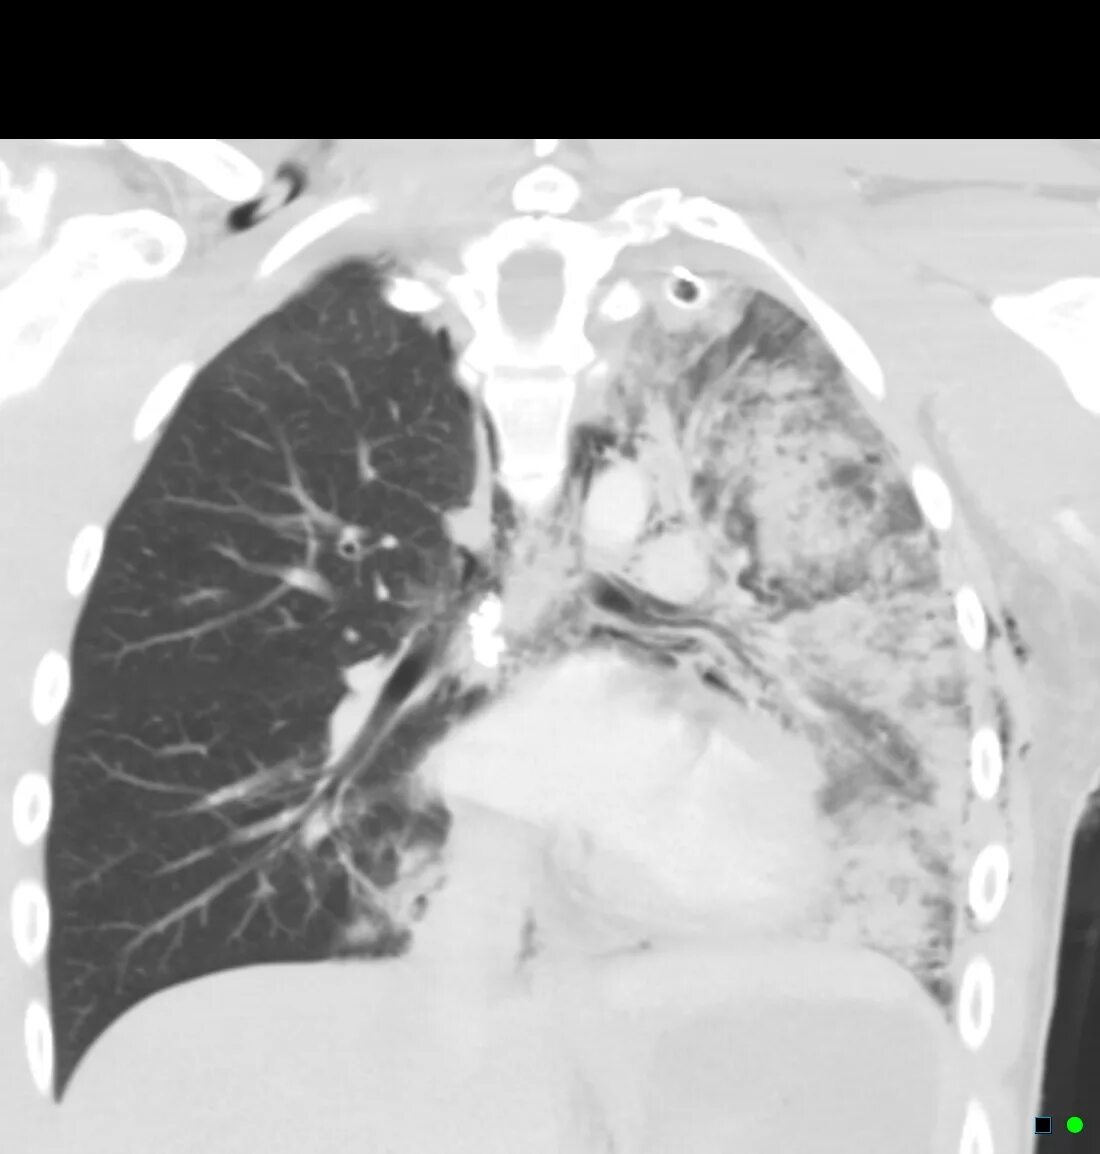

Что такое баротравма при взрыве у человека